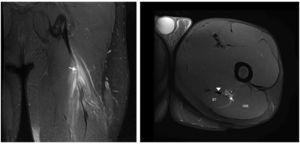

Figura 4 La imagen coronal en T2 con saturación grasa de los isquiotibiales izquierdos durante el seguimiento posquirúrgico muestra el anclaje metálico en la tuberosidad isquiática (punta de flecha) y suturas peritendinosas representadas por artefactos peritendinosos de susceptibilidad magnética (flecha).